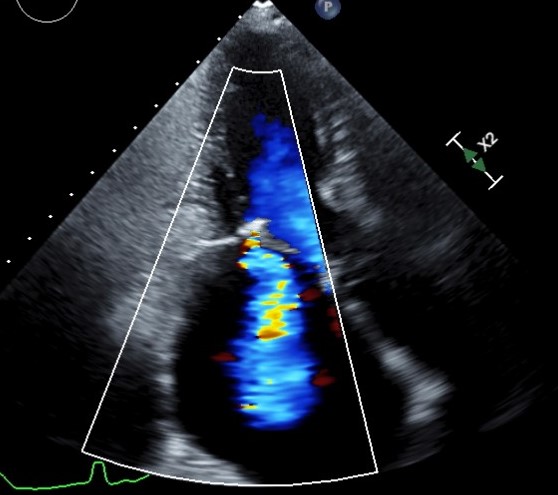

Image- A patient with rheumatic heart disease. Echocardiography helped in diagnosis of valve problems.